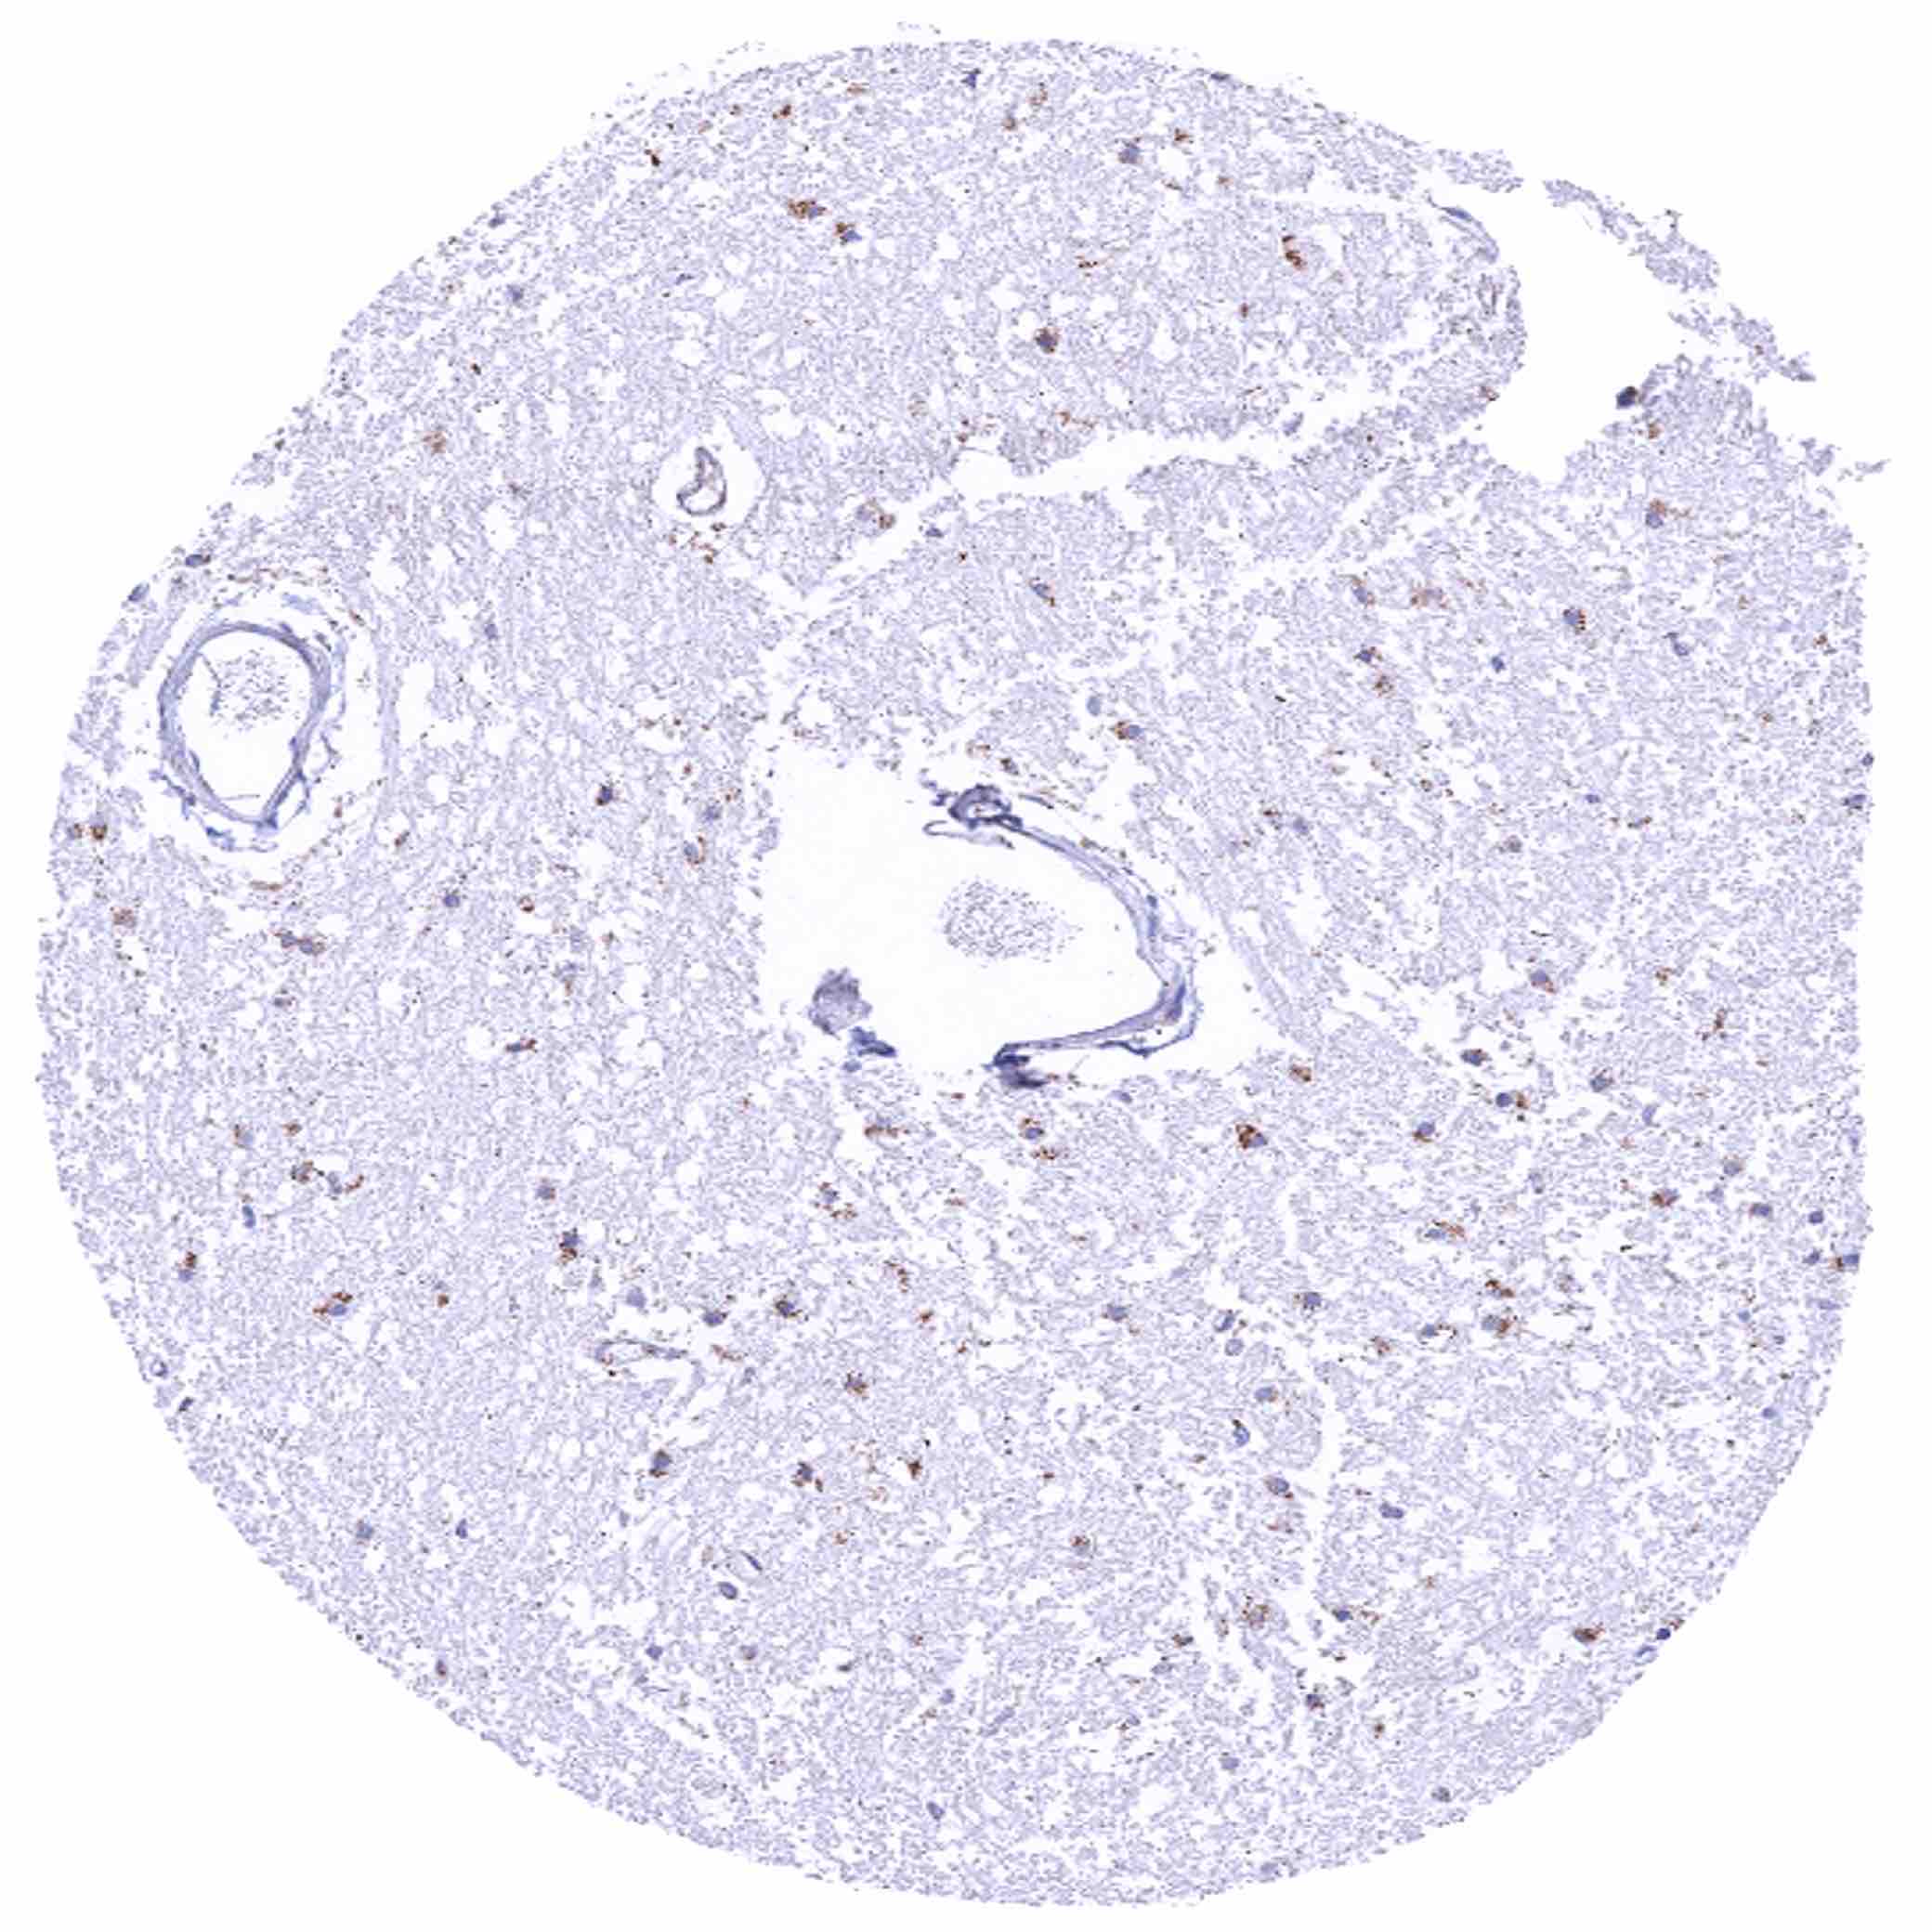

Bone marrow – Granular cytoplasmic SDHB staining is only faint, if at all visible